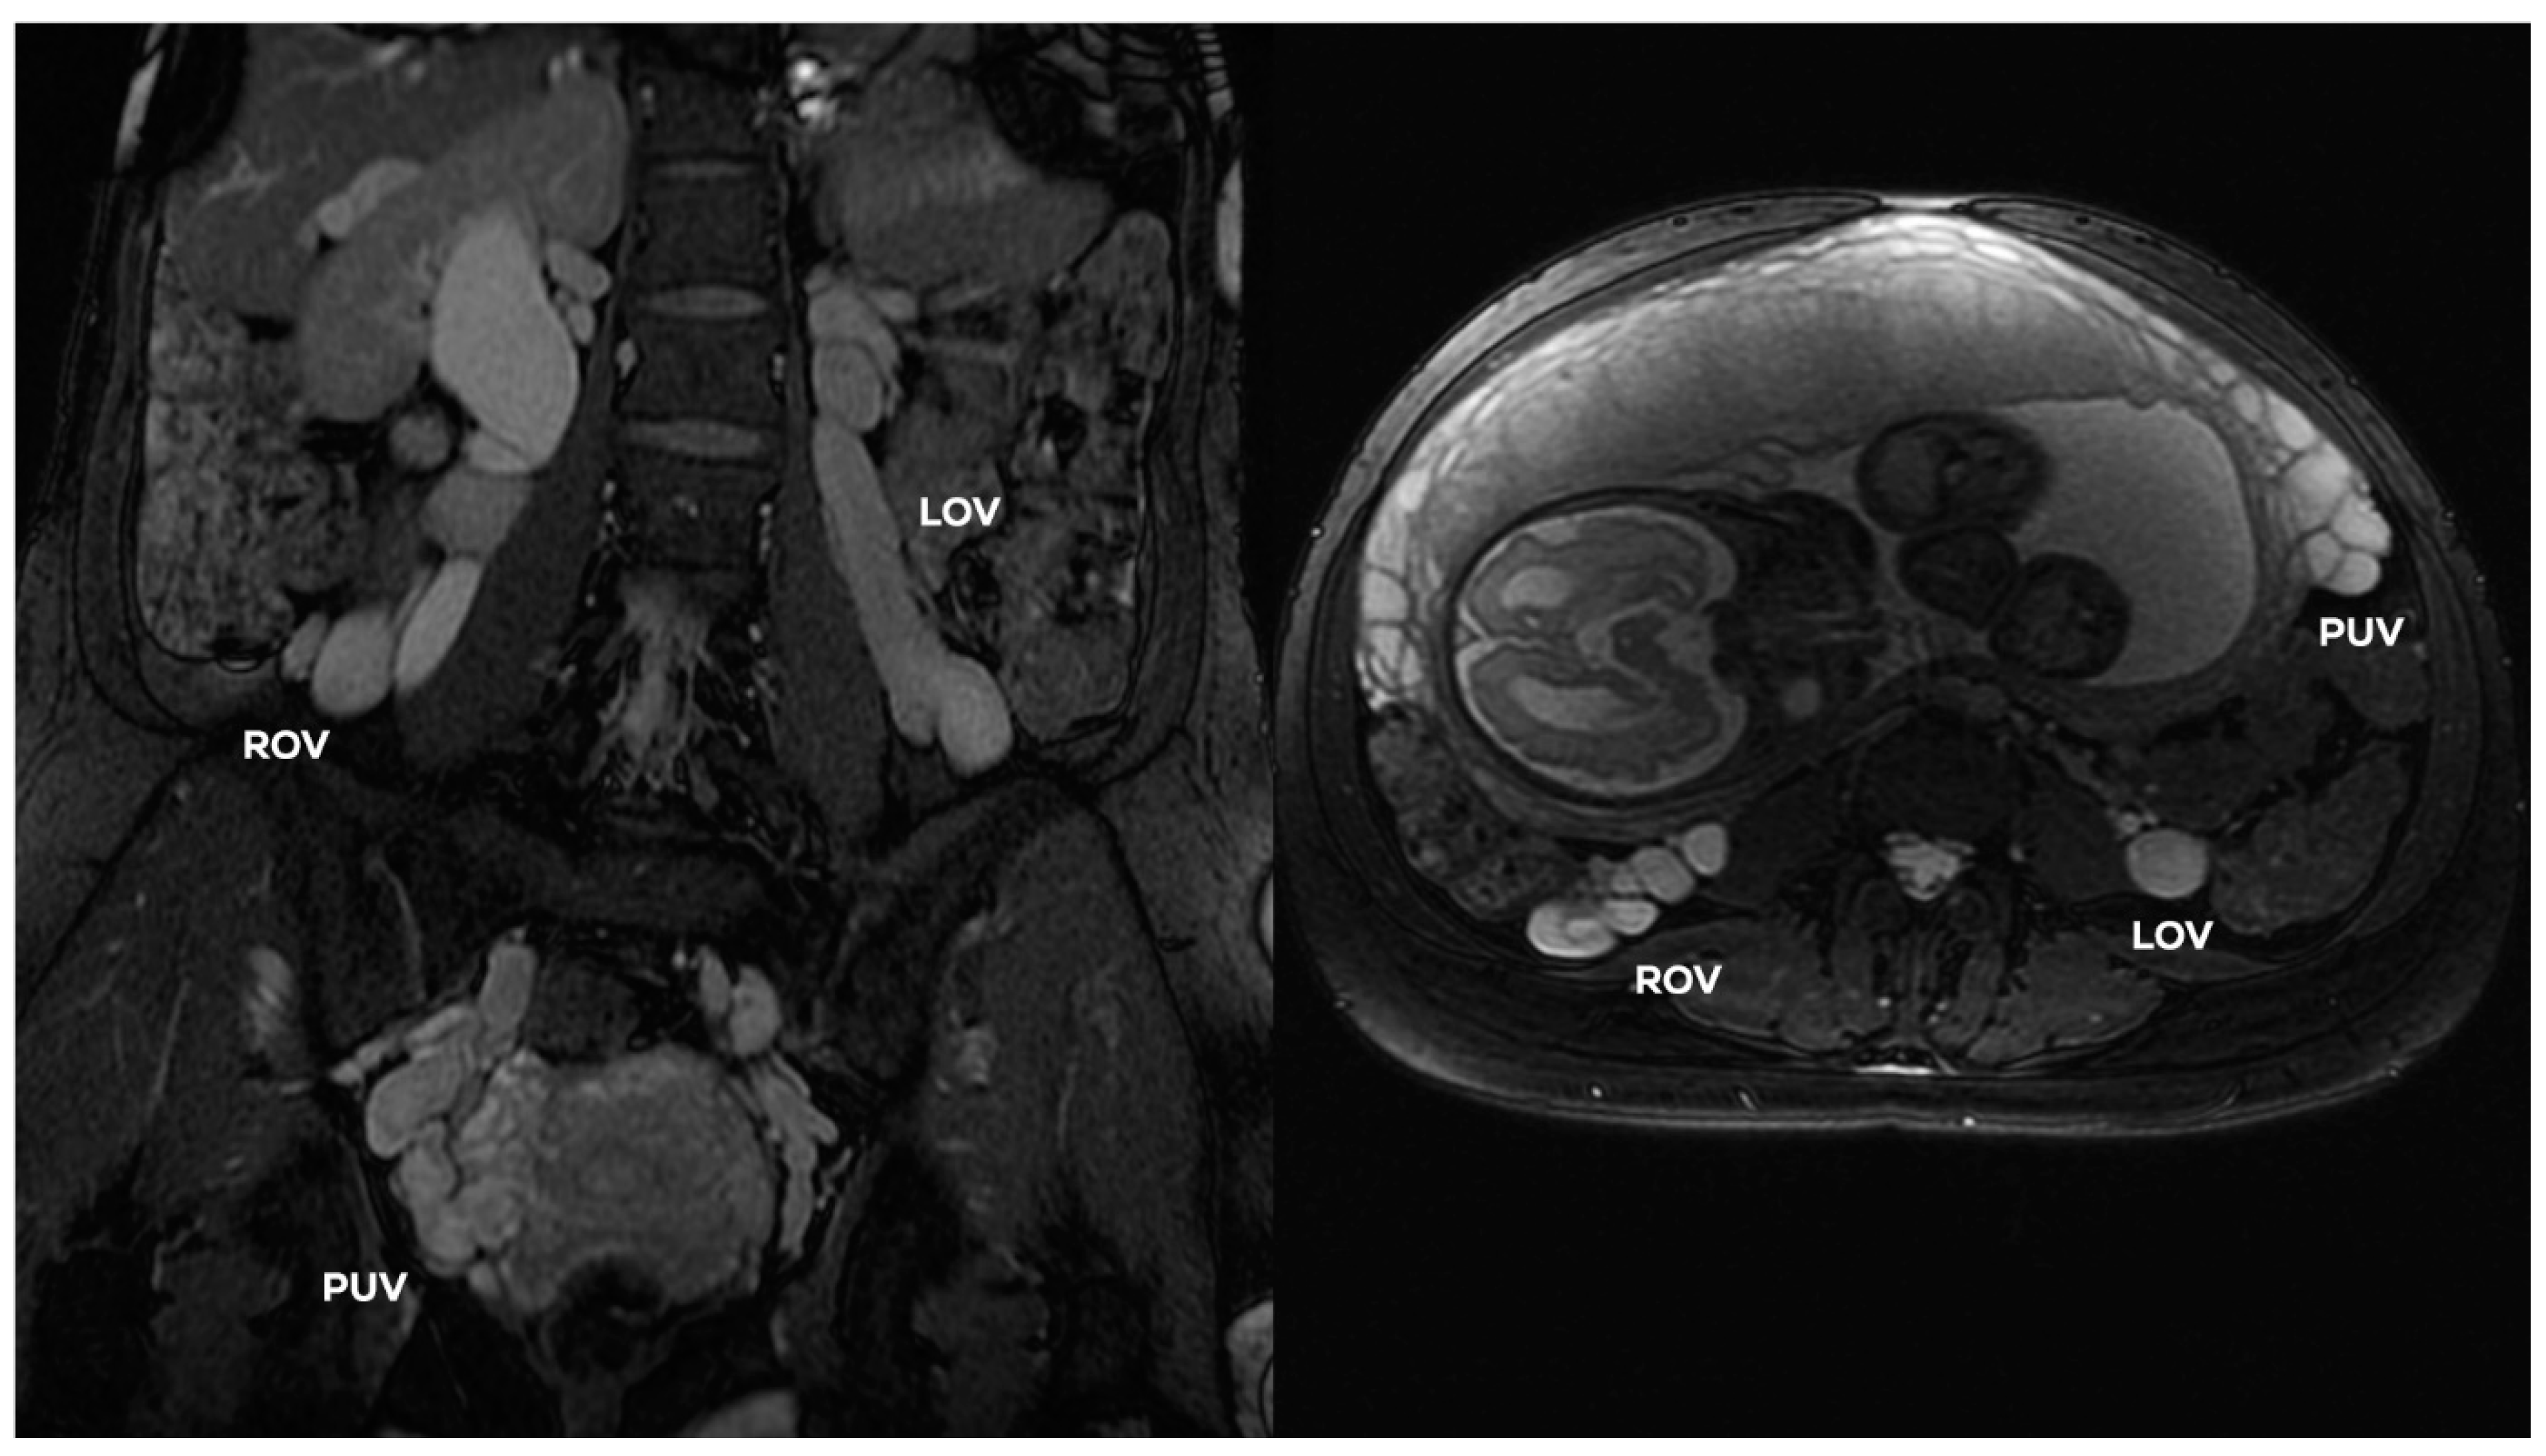

4.2.6. Grade IV (GIV)

In the GIV (Figure 14), a significant distention of the LOV trunk is visible (often ØLOV > 10 mm). This type of venous insufficiency advancement, in the absence of significant anatomical anomalies, is usually found in multiparous women giving birth more than three–four times. The degree of overload in the right ovarian axis in these women during pregnancy is so high (Figure 16) that after delivery a permanent enlargement occurs with the presence of bilateral para-uterine varices and usually a severe secondary overload of the internal iliac vein branches.

In the GIV, the ROV contrasts quite quickly with the discharge of a contrast agent from the IVC trunk through its dilated ostium (often Ø > 5–6 mm). In the case of full-axis insufficiency, the ROV often reaches a diameter of > 8 mm (Figure 17).